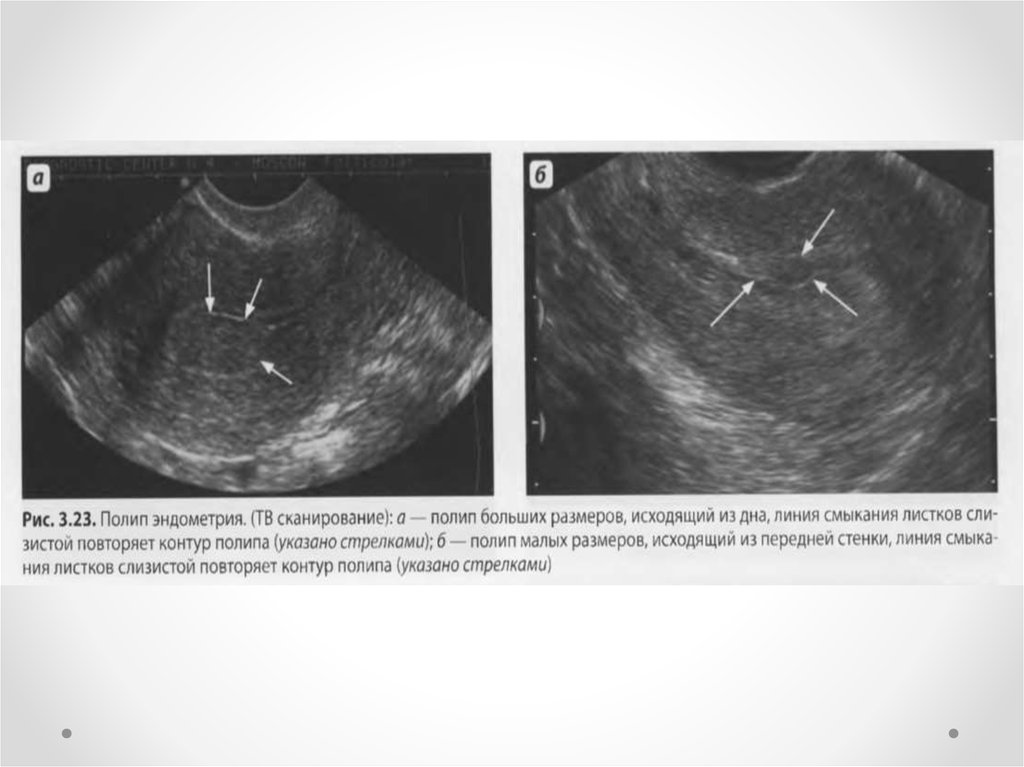

Медицинская диагностика: Гиперплазия эндометрия на УЗИ